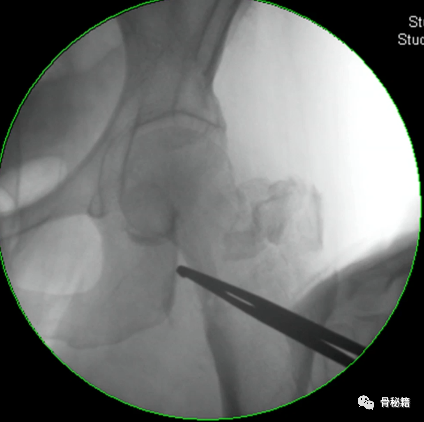

1、进钉点。髓内钉的位置在哪里最合适?

当然是髓腔的最中心,所以髓腔最中心的延长线就是最佳的进钉点。一般位于梨状窝。一个好的进针点可以保证力线,同时进钉后还有复位的作用,如果进钉点出现了偏移,可能整个手术都会有影响。好的开始象征着接下来手术的顺利,一定要取一个好的进针点。

他在正侧位的透视位置我们可以看到位于髓腔中心的延长线上

随着有外翻角的髓内钉的发明,我们现在目前用的可能多是大粗隆顶点进针的了

进针的角度,基本与股骨颈是垂直的角度